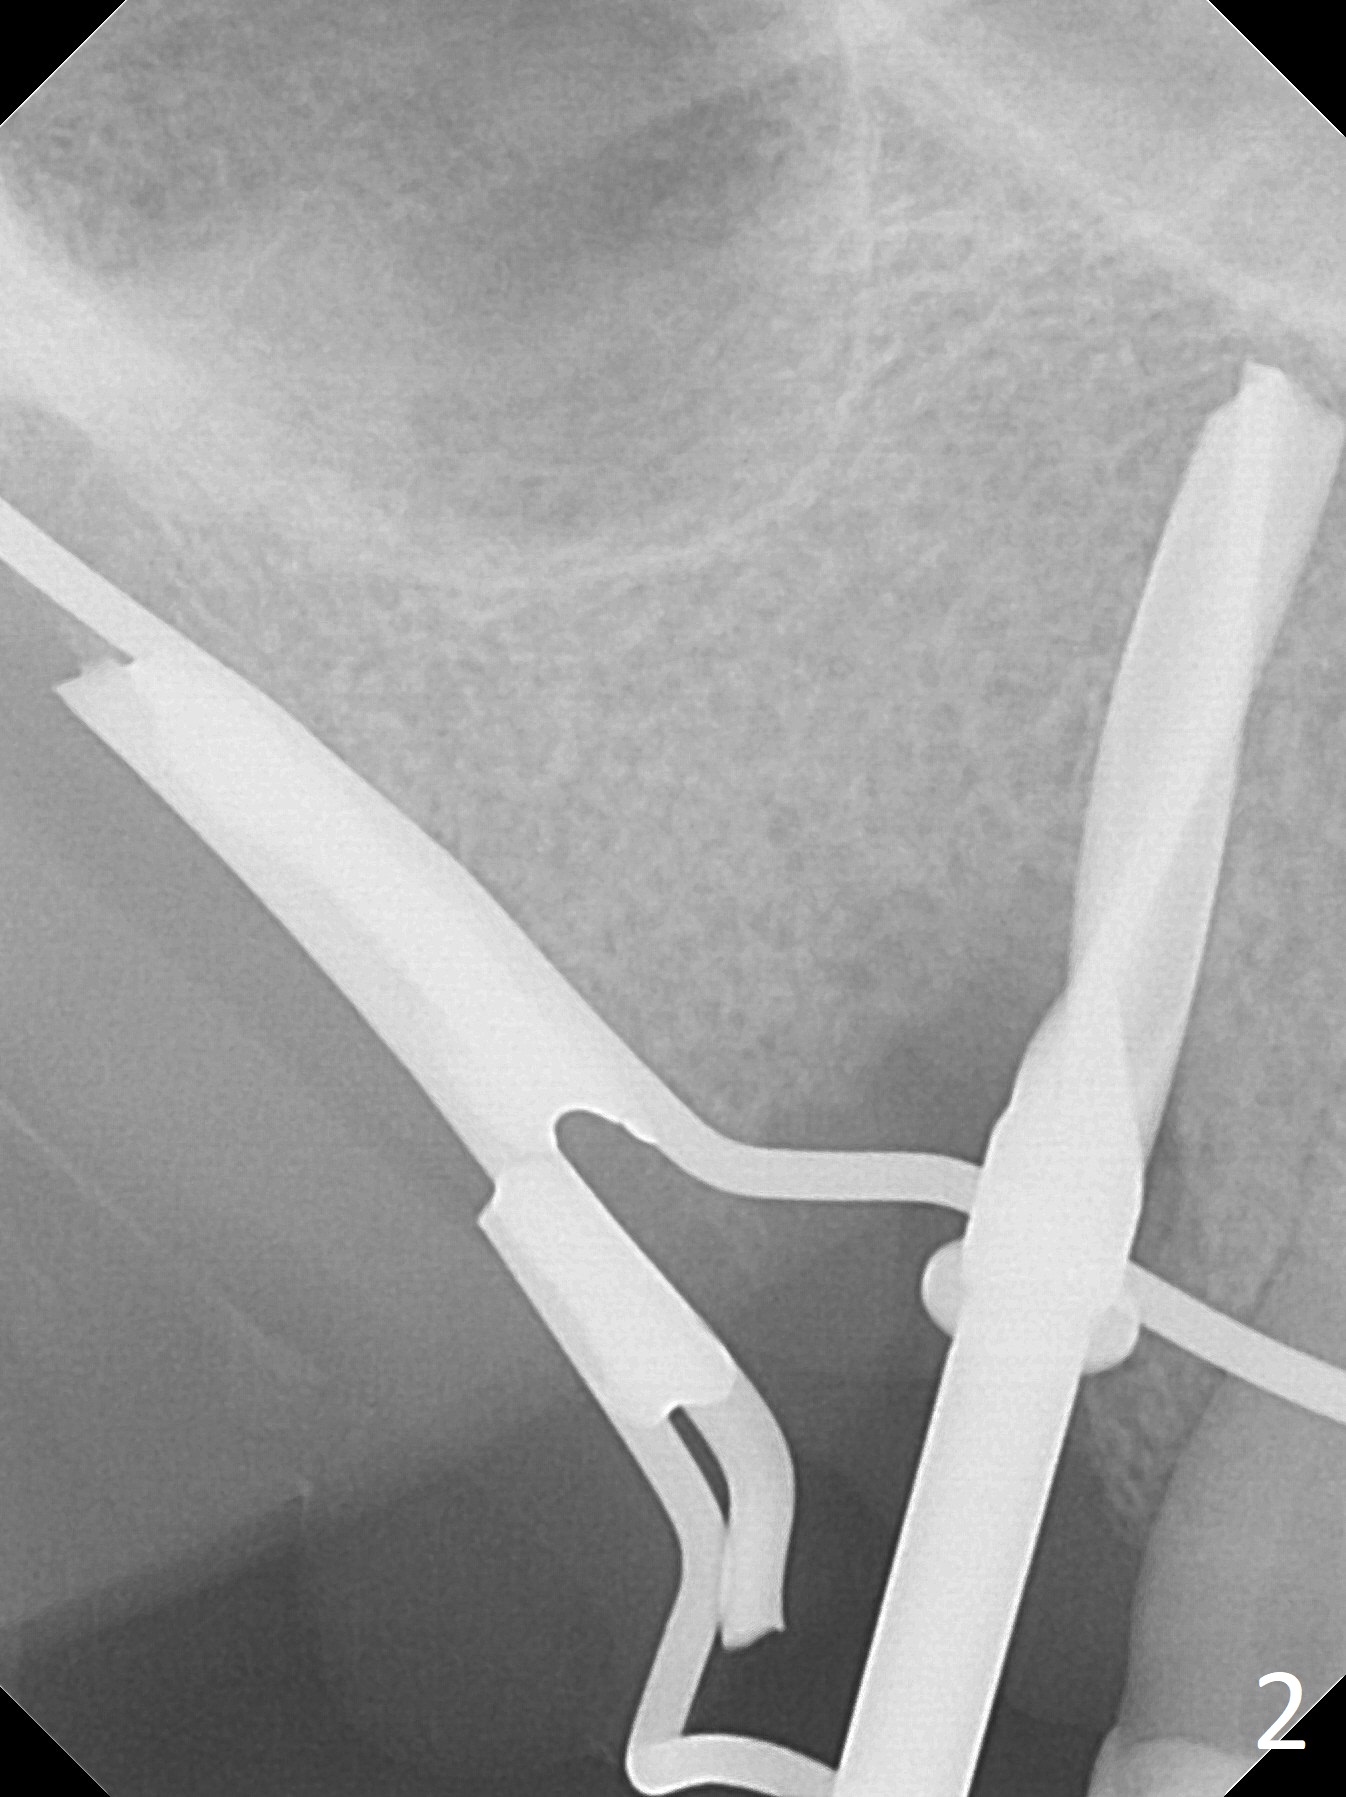

Extraction of the tooth #5 with mobility III reveals no buccal plate and low palatal plate. Osteotomy starts as palatal as possible (Fig.1). The bone density is low. After use of 2.7 mm drill (Fig.2), a 3 mm drill can be inserted into the osteotomy without resistance. A 4x16 mm implant is placed with insertion torque <30 Ncm. When an abutment is placed, the implant is found to have been placed distal. The implant is untorqued for change in trajectory. When a 4.5x7(5) mm abutment is placed, the abutment turns with the underlying implant (Fig.3). The former is kept to be turned with a hand driver until the latter is unable to turn. Following placement of allograft (Fi.g3,4 *), a mini-provisional is fabricated to retain the bone graft and at the same time not to be interfered with when a flipper is in and out. The bone graft in the former socket gap appears to have integrated into the native one 4.5 months postop (Fig.5).